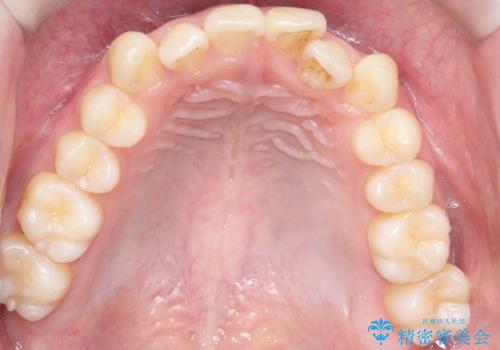

- 前歯の凸凹を主訴に来院されました。

マウスピース矯正も適応でしたが、ワイヤー矯正を希望され治療を行なっております

治療期間も短く大変満足していただきました。